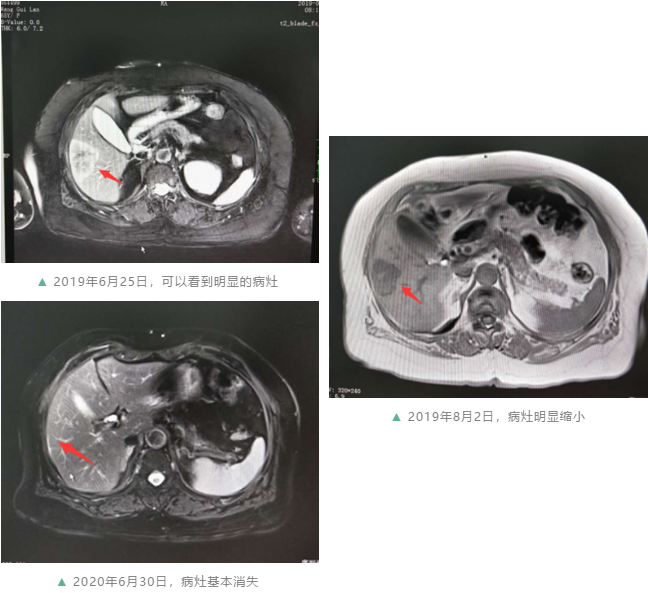

▲ 2019年6月25日,可以看到明显的病灶

▲ 2020年6月30日,病灶基本消失

“患者因为反复便血2月余及腹部肿物入院,确诊为直肠癌晚期,并且发现双肺以及肝脏都出现了转移。”收治患者后,余桂芳主任团队很快就制定出了治疗方案。没有手术机会,就先做药物治疗,一线用药病灶缩小,肿瘤指标下降,但好景不长,随着指标又开始回升,考虑存在耐药,重新讨论确定调整治疗方案。在几个疗程的精心治疗后,奇迹发生了,王阿姨的肺部病灶渐渐消失,肝脏病灶明显缩小,消融、手术跟上,肠道的病灶最终也消失了。